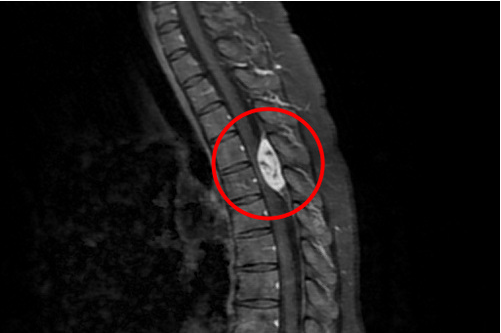

▲經核磁共振檢查,發現廖小姐的胸椎第四、五節空腔有顆三公分大的腫瘤,已嚴重壓迫神經。

38歲廖小姐因連日腹瀉不止由花蓮慈濟醫院腸胃內科收住院治療,但在準備出院前一天,雙腳竟完全無法移動,經核磁共振檢查,發現她的胸椎第四、五節空腔有顆三公分大的腫瘤,已嚴重壓迫神經。隨即轉由神經外科部神經血管介入治療科主任李建輝,以手術清除腫瘤治療,三週後即可靠輔具行走,目前恢復良好。

「三公分的腫瘤不算大,但因為胸椎空腔很小,已經嚴重擠壓到神經原本的空間。」李建輝主任指出,神經相當脆弱,當腫瘤越長越大,將神經越壓越深,直到神經無法再承受壓力,就可能造成永久的損傷;廖小姐從出現腹瀉不適感和脫力感,演變成雙腿完全不能動,再到術前肌力已掉到剩下二分,只能臥床的狀態,整體功能退化得非常迅速。